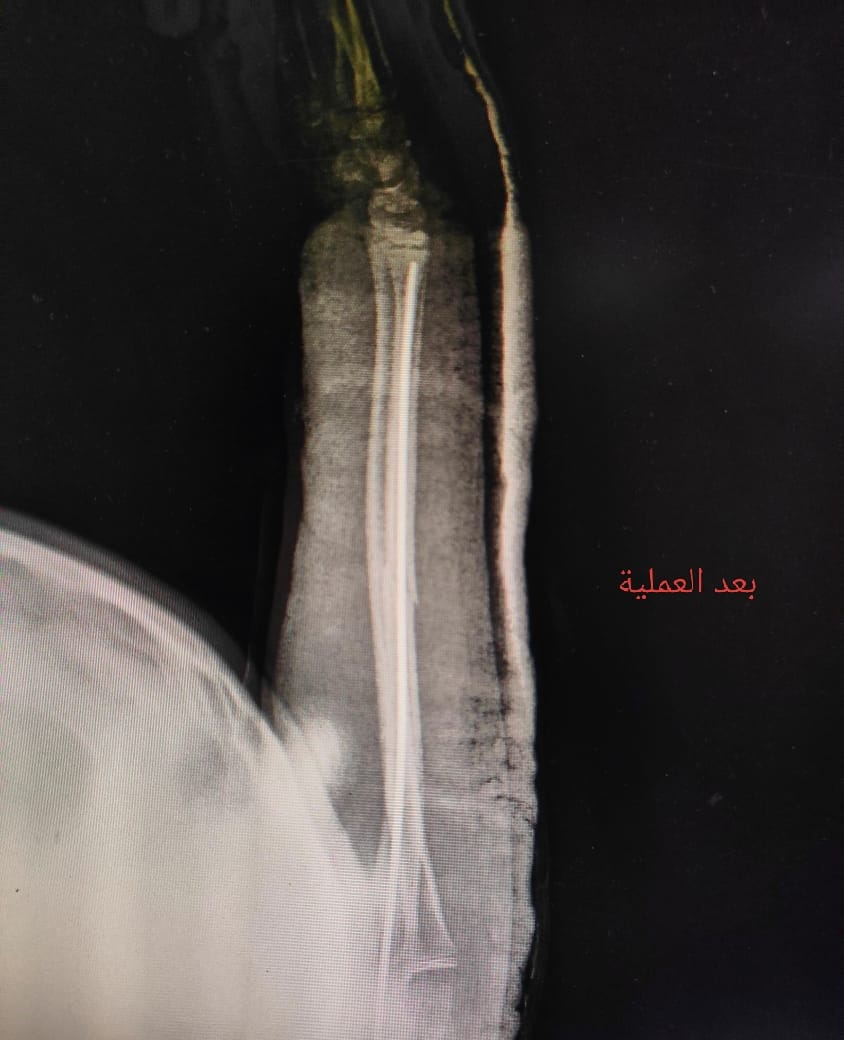

استقبلت مستشفى طلخا المركزي بمحافظة الدقهلية طفلة تعاني من كسر في عظمة الزند الأيسر، حيث جرى التعامل الفوري مع الحالة ونقلها إلى غرفة العمليات لإجراء التدخل الجراحي اللازم.

وذلك تنفيذًا لتعليمات الدكتور خالد عبد الغفار نائب رئيس الوزراء ووزير الصحة واللواء طارق مرزوق محافظ الدقهلية وبرعاية الدكتور حمودة الجزار، وكيل وزارة الصحة بالدقهلية، وإشراف مباشر من الدكتور السيد فاروق، وكيل المديرية للطب العلاجي،، والدكتورة لاميس حمدى، مدير مستشفى طلخا المركزي، حيث تم إجراء العملية بنجاح وتركيب مسمار نخاعي مرن بالزند الأيسر.